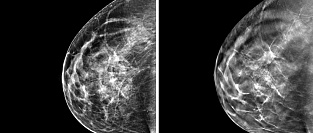

Маммография в старшей возрастной группе. Есть ли польза?

В середине 1960-х годов в США после введения маммографии в качестве скрининга, смертность от рака молочной железы (РМЖ) снизилась на впечатляющие 25%. С тех пор маммография прочно вошла в медицинскую практику в качестве золотого стандарта раннего выявления рака груди. Подробнее: МАММОГРАФИЯ. ИНФОРМАЦИЯ ДЛЯ ПАЦИЕНТОВ